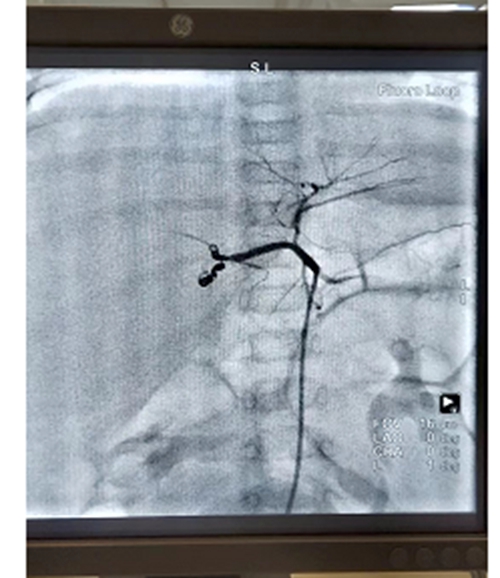

为让患儿得到及时治疗,破解治疗难题,儿外中心邀请医院副院长、心内介入知名专家泮思林教授进行会诊,决定采用先通过高选择性血管栓塞术介入,对肿瘤的供血血管进行栓塞,使瘤体变小;再进行外科手术,完整切除肿瘤的治疗方案。

患儿出生仅3个月,年龄小、体重轻,血管细,介入手术难度极大。术前,各学科对各种可能出现的情况制定了应急预案。术中,泮思林教授凭借精湛技术和丰富经验,顺利将弹簧栓精准送达拟定部位,肝母细胞瘤主要动脉血管被充分阻断。术后,患儿肿瘤瘤体明显缩小,大大减少了后续切除手术中瘤体出血风险。